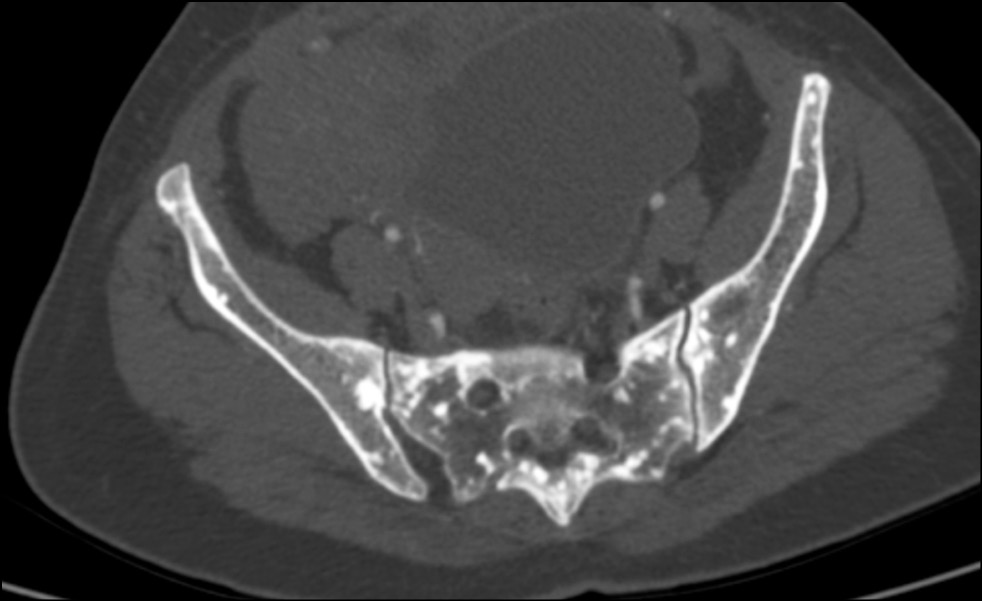

A 43-year-old female patient was taken to the emergency room by ambulance after experiencing transient loss of consciousness. The initial evaluation consisting of history, physical examination, 12-lead electrocardiogram and laboratory tests did not reveal any abnormalities; thus, a total-body computed tomography (CT) was performed. The CT scan showed multiple small sclerotic foci bone islands, scattered throughout the thoracic (Figure 1a) and lumbar spine (Fig. 1b), ribs, pelvic bone (Fig. 2), sacrum (Fig. 3) and bilateral proximal femur (Fig. 4). All bones were free of any cortical erosion or periosteal reaction. No other signs, such as rubor or edema, were noticed; moreover, the patient did not describe any numbness, tingling and weakness in the legs or other parts of the body.

Fig. 3. Transverse cross-section computed tomography scan passing through the sacroiliac joints. It shows small, sclerotic, round opacities distributed symmetrically along sacrum, hip bone, and sacroiliac joints.